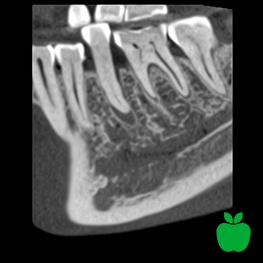

Rozdzielczość HD

wielkość woksela 150 μm, dawka pacjenta ~134 μSv

Bardzo drobne szczegóły, duża dawka.